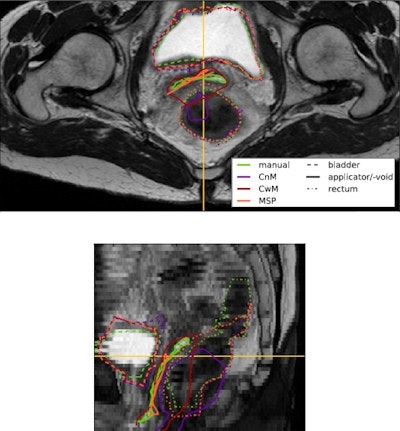

In deformable image registration, a so-called moving image (in this case, the external-beam MRI) is warped to the fixed image (the applicator-containing brachytherapy MRI). The method proposed by the Utrecht team exploits the fact that the missing structure can be considered to have zero volume after mapping it to the external-beam image. By introducing a geometrical penalty term that minimizes the volume of the void left by the applicator's removal, this mapping can be established (Physics in Medicine and Biology, 2 July 2014, Vol. 59:15, pp. 4033-4045).

Berendsen and colleagues incorporated their proposed missing structure penalty (MSP) term into the general purpose nonrigid registration framework from the elastix toolbox. They tested the resulting algorithm on 18 pairs of cervical MRI scans -- each pair constituting a fixed image with the applicator in place and a moving image without an applicator.

The researchers evaluated three types of registration: conventional registration with an applicator mask (in which masked voxels in the external-beam image do not influence registration); conventional registration without an applicator mask; and registration including the proposed MSP term. The mapping established by each was then used to transform all manual delineations of the fixed image to the moving image.

These transformed delineations (U') were then compared with gold-standard manual delineations (Ugold) of the bladder and rectum (organs-at-risk), and the surface of the void (a combination of vaginal and uterine walls) in the external-beam image. The applicator was also manually delineated for use in the proposed MSP term and the mask-based registration.